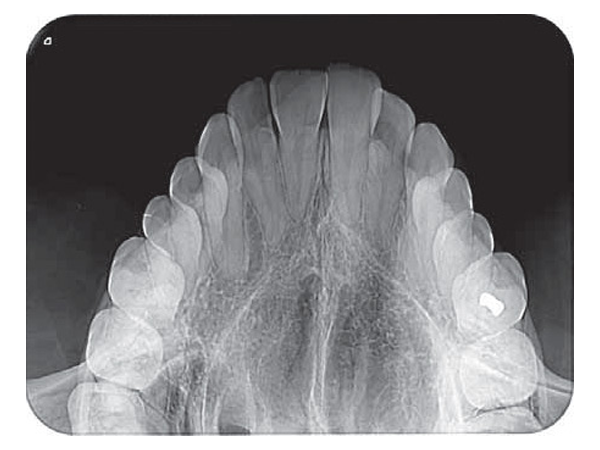

Chất lượng hình ảnh rõ nét

Nhờ công nghệ PCS, VistaScan Mini có thể giúp giải quyết các vấn đề về sâu răng D1, các tổn thương về nội nha xuống đến ISO 06. Với độ phân giải hình ảnh 22 lp/mm, 16-bit (65.536) thang xám.